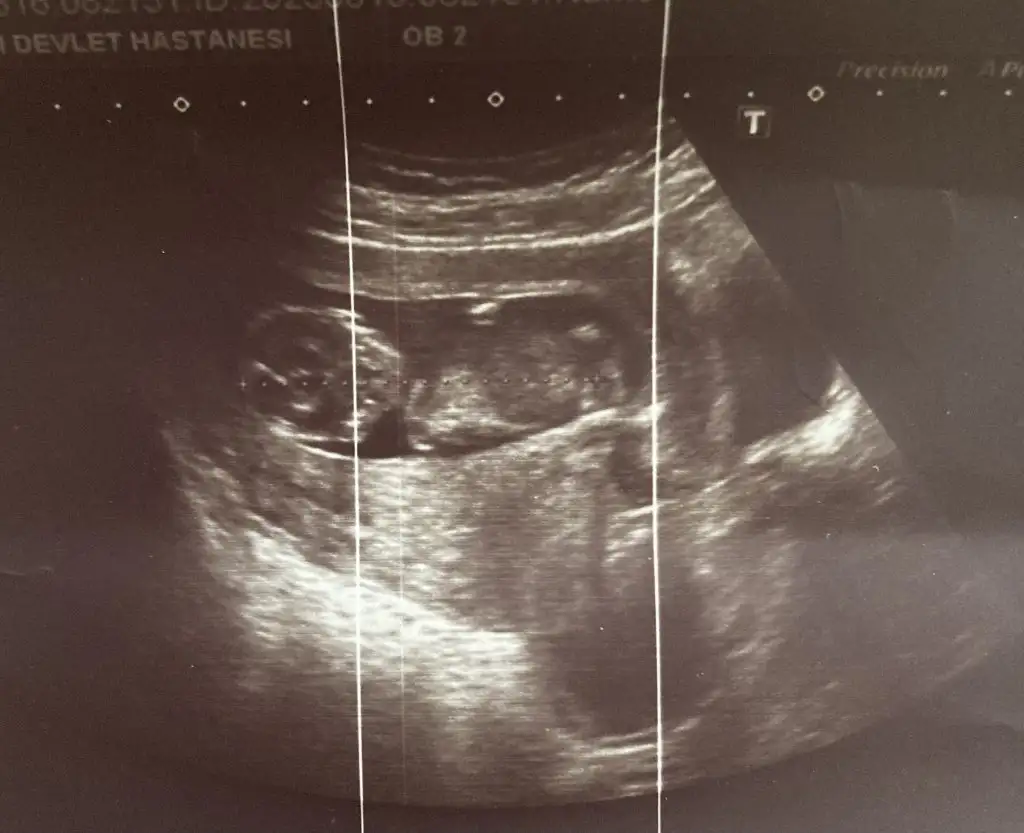

Benim bebeğimi de yorumlar mısınız rica etsem. Ultrason görüntülerim pek net değil ama sırasıyla 6 -9 - 12 haftalkk ekliyorum. Teşekkür ediyorum şimdiden N Nakafile

Kız bebeğine benziyor. Hayırlısı ile gelsin. Öğrenince yazarsınız bakalım doğru tahmin mi olacak. Nub kısmı düz çünkü bebeğin